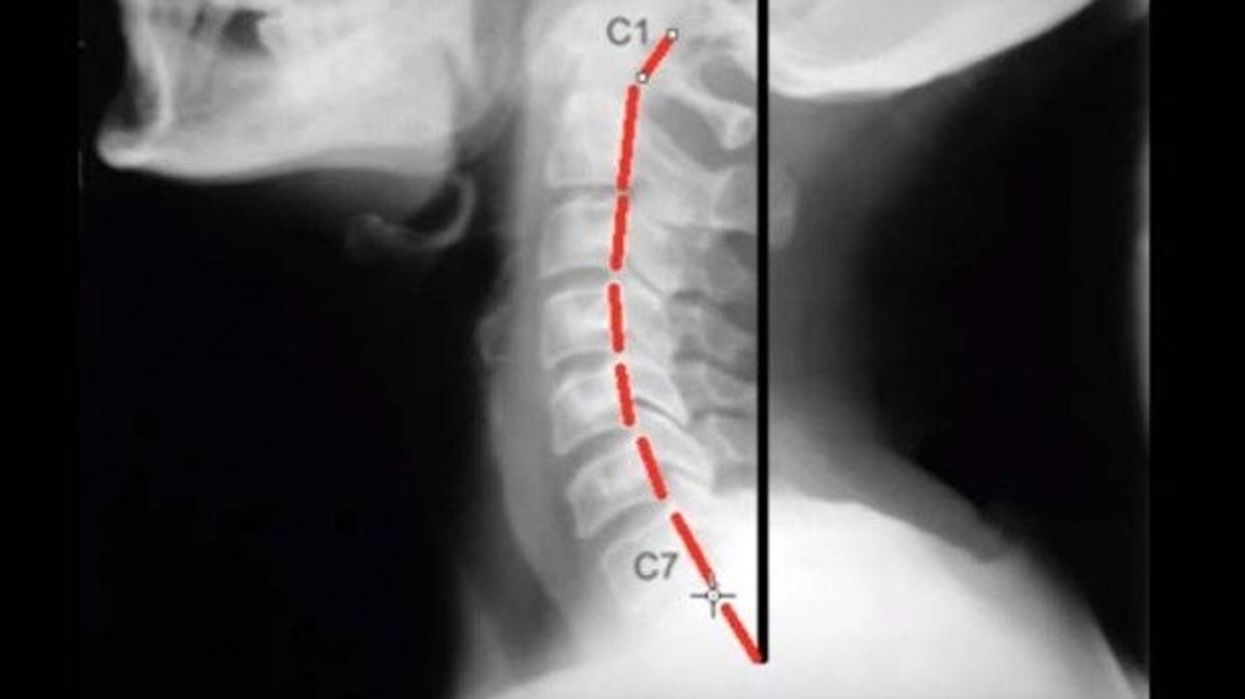

Në video-klipin tjetër mund të shihni si duket xhirimi i qafës e cila qëndron drejt, përkatësisht pozita natyrale e unazave.

Ndërkaq, këtu shihet pozita e unazave kur qafa është e relaksuar.